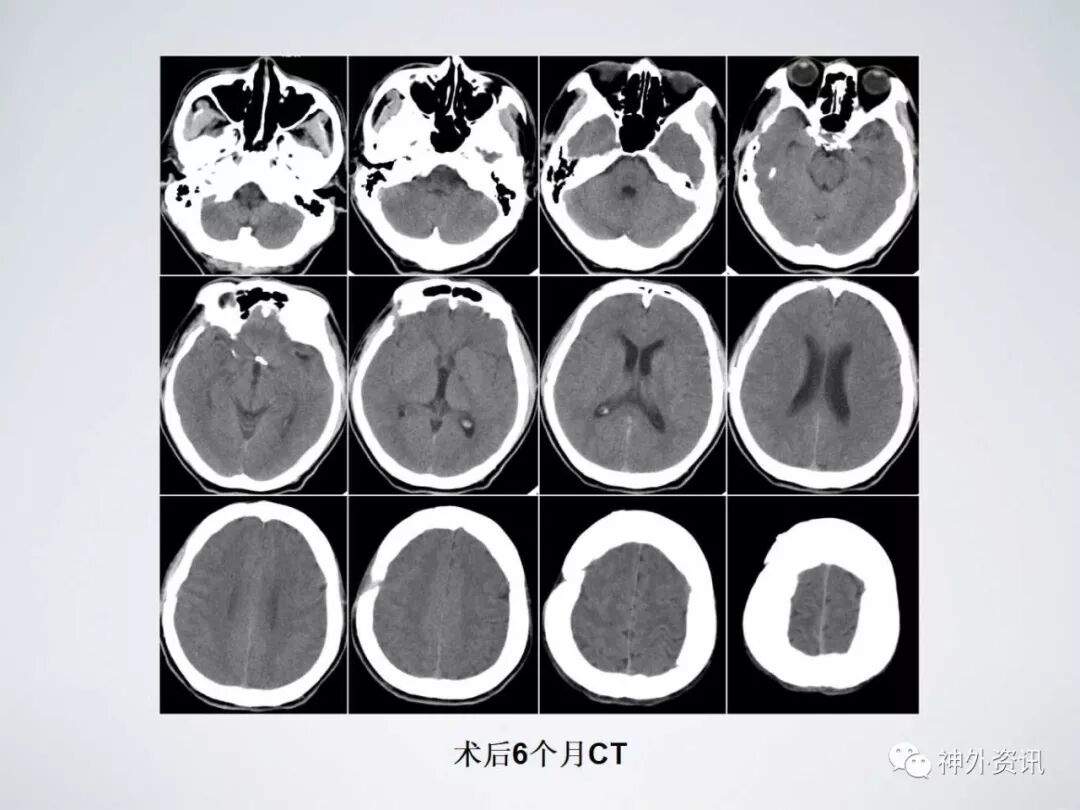

术后6个月